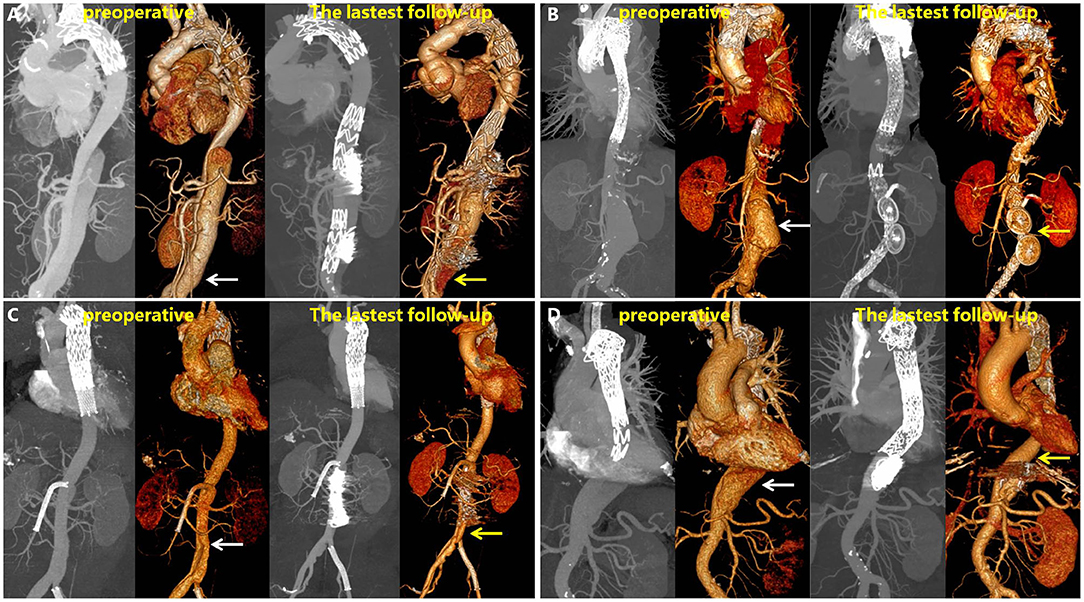

Figure 6 shows the representative images of the anatomic changes over time in the MIP mode and three-dimensional reconstruction of CTA before (preoperative) and after RBS (latest follow-up). A video of the three-dimensional reconstructions during the preoperative period and the angiography results before RBS and at the latest follow-up is available in the Supplementary Materials. One typicle case of negative aortic remodeling, denovo aortic dissection and aortic rapture in non-RBS group can be seen in Supplementary Figure 1.

Figure 6. Maximum intensity projection (MIP) and 3D reconstructions of CTA in patients before and after RBS. White arrow points toward dilatation of the FL, and yellow arrow toward thrombosis formation in the FL or shrinking of the FL. (A) Patient's left renal artery was involved, and a slight endoleak was observed at 31 months. (B) Patient's left renal artery was involved, the FL disappeared at 43 months on 3D reconstruction images. (C) Patient's superior mesenteric artery was involved, the FL shrinked at 28 months. (D) Patient's celiac trunk was involved, the FL shrinked at 25 months.